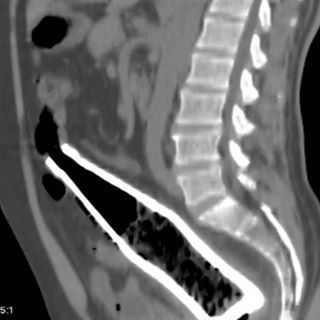

据统计,在急诊室中,男性“失物招领”的情况是女性的40倍,大部分失物是在肠道中被发现的,而且花样繁多……